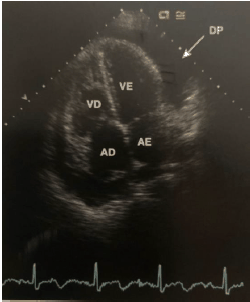

A imagem ecocardiográfica abaixo pode evoluir para uma emergência cardiológica que pode ter consequências graves, incluindo a morte. Baseado na figura abaixo, assinale a alternativa correta.